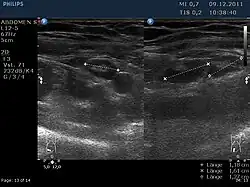

Vergrößerte Lymphknoten im rechten Unterbauch (Ultraschallbild)

Das klinische Bild ähnelt dem der Appendizitis („Blinddarmentzündung“), die – wie der Morbus Crohn – zu den Differentialdiagnosen der Lymphadenitis mesenterialis gehört. Neben Fieber und Druckschmerz im rechten Unterbauch finden sich oft auch ein auffälliger Befund in der Rektaluntersuchung und eine rektal-axilläre Temperaturdifferenz. Der spezifische Erregernachweis gelingt gelegentlich aus dem Stuhl oder durch Nachweis des Anstiegs der Antikörpertiter. Bei der unspezifischen Lymphadenitis mesenterialis findet sich häufig eine Mitbeteiligung anderer Lymphknotenstationen oder der Tonsillen. Mit hochauflösender Sonografie lassen sich die vergrößerten mesenterialen Lymphknoten oft darstellen.